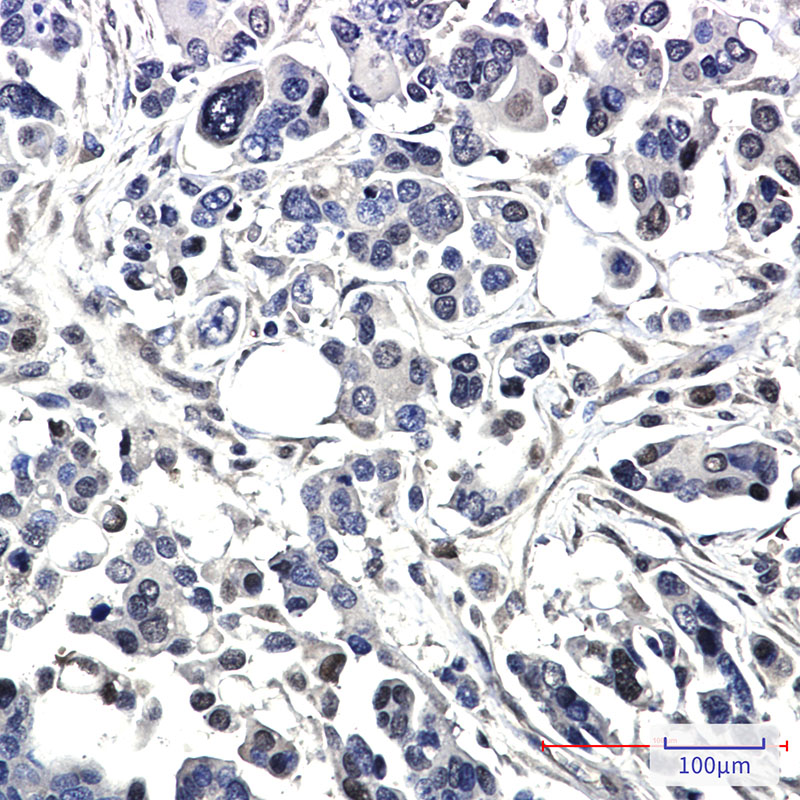

| WB, IHC-P |

| Dilution | WB~~1:500-1:1000 IHC-P~~1:50~200 |